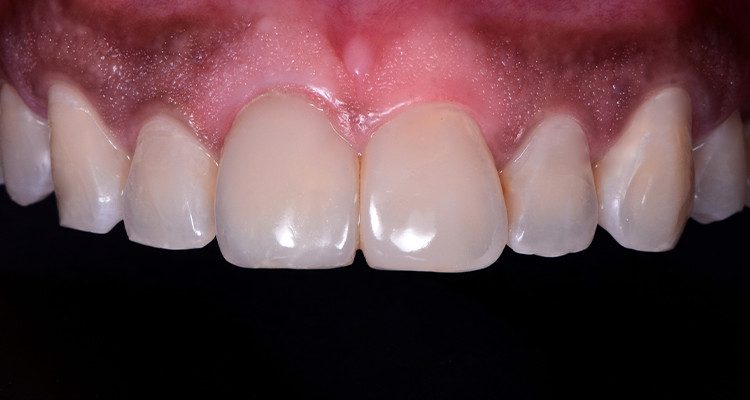

1 | Imagem intraoral do sorriso em oclusão

29 | Aspecto final mostrando uma harmonia de forma e cor dos dentes 11 e 21 com os demais dentes.

🔗Saiba mais sobre a linha de endodontia!